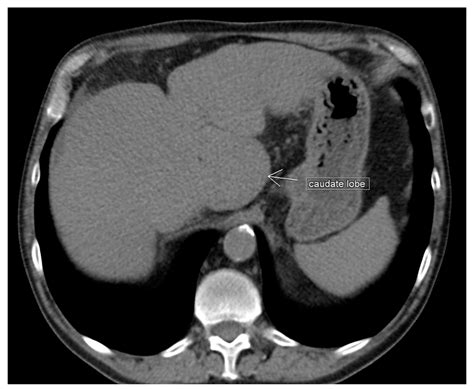

The liver is divided into several lobes, each with distinct functions and anatomical features. The Liver Caudate Lobe is one of these lobes, located in the posterior and superior aspect of the liver. It is situated between the inferior vena cava and the ligamentum venosum. The Liver Caudate Lobe is unique because it receives blood supply from both the hepatic artery and the portal vein, making it a critical component of the liver's vascular system.

The Liver Caudate Lobe is further divided into two segments: the caudate process and the paracaval portion. The caudate process extends to the left and is in close proximity to the ligamentum venosum, while the paracaval portion is adjacent to the inferior vena cava. This anatomical positioning allows the Liver Caudate Lobe to play a significant role in the liver's overall function.

Diagnosing disorders of the Liver Caudate Lobe involves a combination of imaging techniques and laboratory tests. Imaging studies such as ultrasound, computed tomography (CT), and magnetic resonance imaging (MRI) can provide detailed visualizations of the liver and its lobes. These imaging techniques can help identify abnormalities, such as tumors or cysts, in the Liver Caudate Lobe.